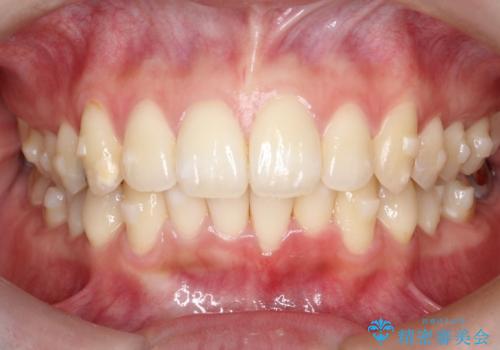

- 前歯のでこぼこが気になると来院されました。

奥歯の噛み合わせは綺麗に噛んでいたため、前歯の叢生(でこぼこ)を、短期間で治療完了するように計画しました。

奥歯の噛み合わせは整っていたため、前歯の並びを美しく修正することに専念できました。マウスピース矯正による治療で短期間で改善しました。